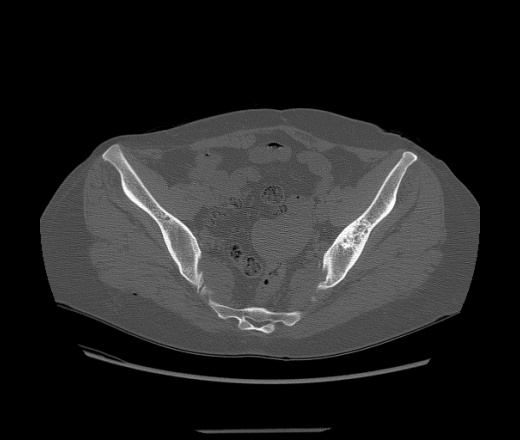

Добрый день уважаемые коллеги. Пришла сегодня на исследование молодая пациентка (37 лет), жалоб нет, есть  изменения в левой подвздошной кости, кортикальные слои сохранены, есть небольшое вздутие кости, по перефирии есть аналогичные, но гораздо меньшие изменения. До этого делала в другом заведении в 2014 году описали как участок кистовидной перестройки, судя по описанию размеры примерно такие же, может чуть чуть побольше. На что может быть похоже? заранее спасибо.

Ну видимо на контроль пришла, в 2014 году нашли при обследовании, но без понятия зачем ее тогда смотрели если жалоб и тогда не было.  В анамнезе есть образование надпочечника по КТ-признакам доброкачественное с 2009 года, округлое, гиподенсивное с четкими ровными конутрами, не накапливающее контрастное вещество, но опять же не у нас обследовалась. Просто без понятия чего в заключение выносить.

на фиброзно-кистозную дисплазию не может быть похоже?

Фиброзная дисплазия?

Не исключено. Ещё думал о сакроилиите.

+1 к фиброзной дисплазии.

Я тоже за фиброзную дисплазию.